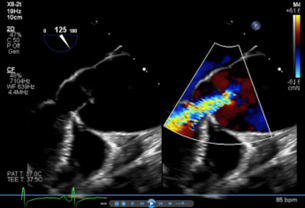

Brain and neck magnetic resonance angiography (MRA) showed no acute or significant vascular abnormality. Transesophageal echocardiogram showed severe aortic regurgitation, trileaflet thickened aortic valve, enlarged ascending aorta 45 mm, normal left ventricular systolic function and patent foramen ovale (Figure 1, Figure 2 and Figure 3). Calculated aorta size index (aortic size cm/body surface area m2) was moderate-severely increased, 2.7 cm2/m2. Mild immobile atherosclerosis of the aorta was noted.

Due to severe aortic regurgitation with limiting dyspnea on exertion, aortic valve replacement surgery was recommended, with adjunctive aortic root replacement for aortic aneurysm and closure of PFO. Pre-operative cardiac catheterization showed normal coronary arteries.